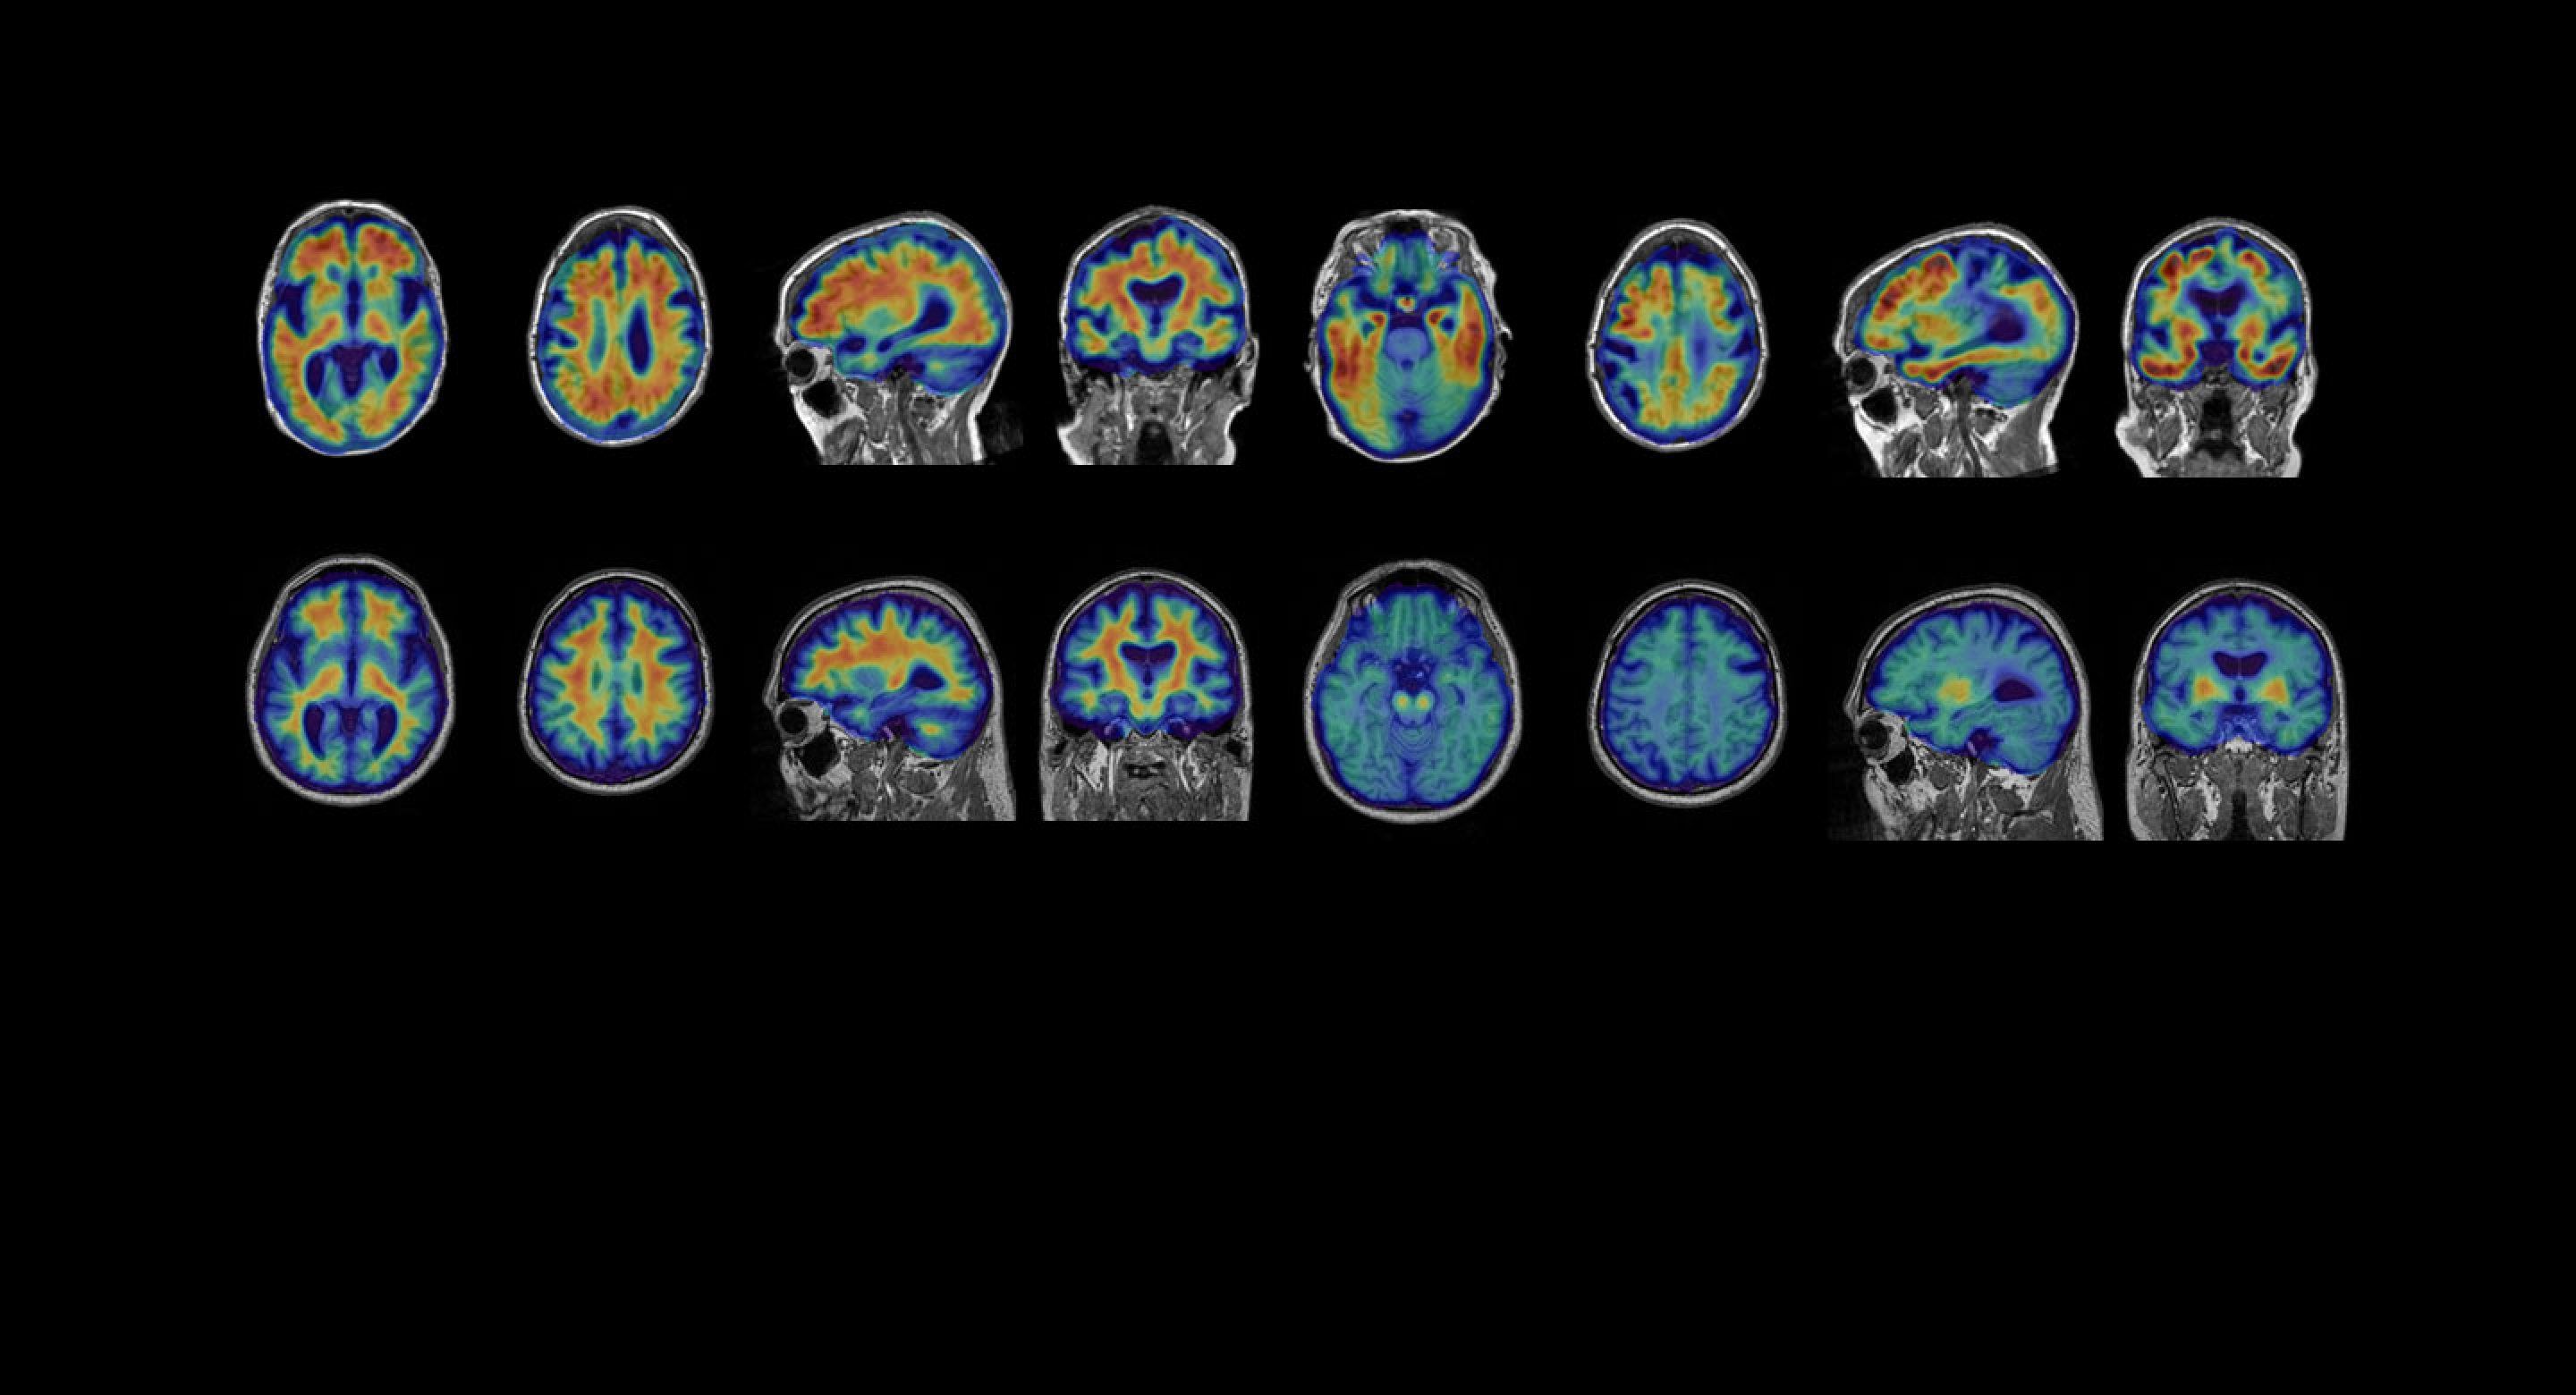

Gil Rabinovici, MD: One potentially serious adverse effect is amyloid-related imaging abnormalities (ARIA), which occur in patients treated with anti-amyloid therapies. This refers to swelling or microscopic bleeds in the brain. ARIA will need to be monitored closely with serial MRI, especially as patients initiate treatment. However, in the lecanemab trial, it was asymptomatic in 80% and very rarely associated with serious symptoms. The swelling typically resolves spontaneously and most patients can resume treatment. A genetic test will likely be recommended, since some variants of APOE, a gene that increases the risk of Alzheimer’s, are associated with a higher risk of ARIA.